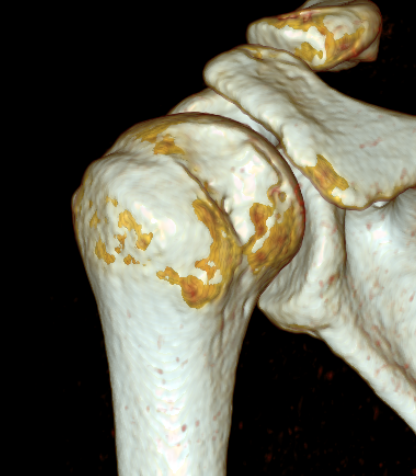

Bony bankart 3D CT with humeral head subtraction

Hill Sachs

Hill Sachs 3D CT

Anterior glenoid bony deficiency - inverted pear appearance